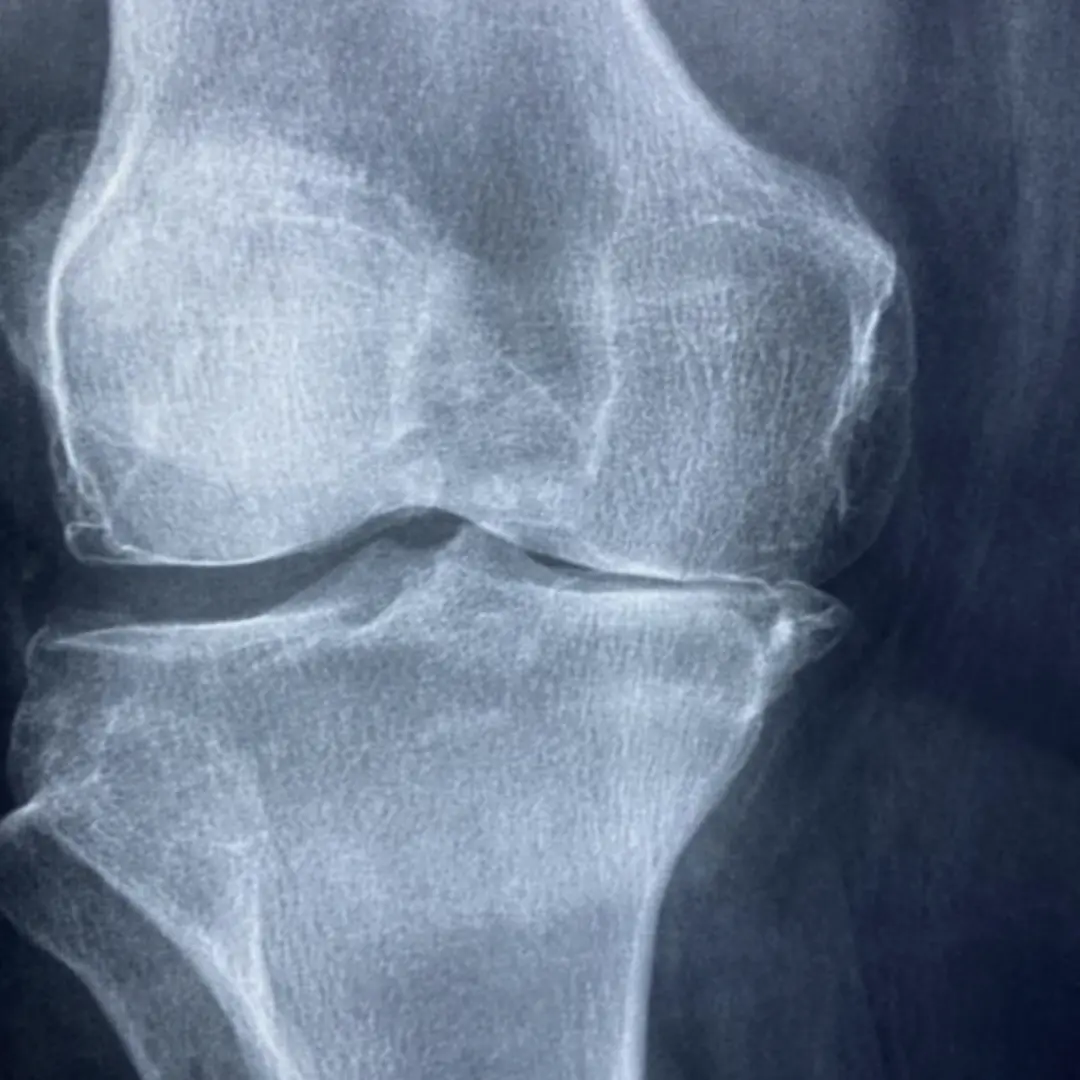

- Q: 십자인대 파열 진단은 어떻게 하나요?

- A: 병력 청취, 신체 검진, X-ray, MRI 등의 영상 검사를 통해 십자인대 파열 여부 및 파열 정도를 정확하게 진단할 수 있어요.